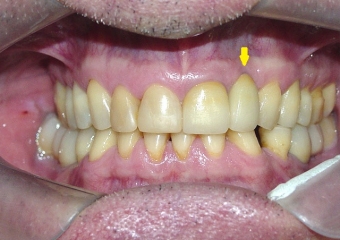

Prótese fixa em porcelana sobre implante Cone Morse

Imagem final, do caso terminado em fevereiro de 2013